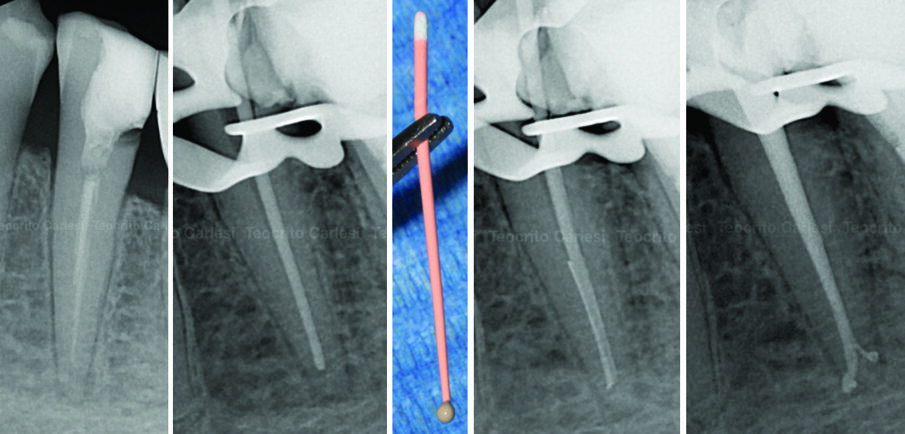

All’esame radiografico le otturazioni appaiono dense ed omogenee, la guttaperca mostra un buon adattamento alla morfologia endodontica, determinando un buon riempimento delle irregolarità del sistema canalare. Sono stati evidenziati la presenza di canali laterali ed uscite apicali multiple. Figg. 8a-8e molare superiore, Figg. 9a-9e molare inferiore, Figg. 10a-10c molare superiore, Figg. 11a-11d anatomie complesse premolare curvo e Figg. 12a-12d ottavo.

Fig. 9 - Ritrattamento canalare 3.7 controllo a 7 anni.